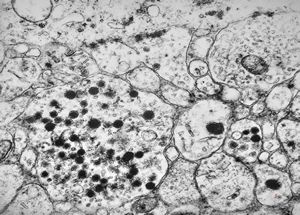

F, 68y. | APUD carcinoma mammae